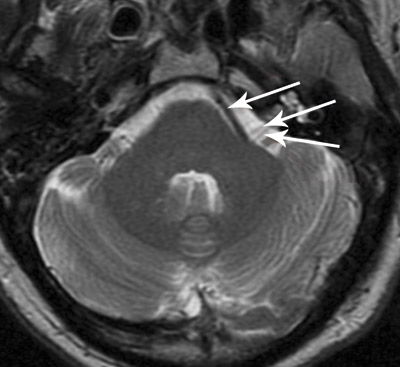

Pasienten har hemifaciale spasmer. Diagnosen stilles på klinisk grunnlag og er basert på observasjon av anfallsvise, ensidige, oftest kortvarige spasmer som kun ses i muskulatur innervert av n. facialis. Prevalensen hos voksne er ca. 10/100 000. Spasmene skyldes som regel mekanisk irritasjon av et blodkar på facialisnerven intratekalt. Hos pasienten på videoen viste MR en slynget arterie nær venstre n. facialis (bildet). Differensialdiagnose er enkel partiell epilepsi og motoriske tics. Her vil også muskler som ikke er innervert av facialisnerven kontraheres. Ticsene er oftest av kort varighet uten spasme, i motsetning til ved hemifacial spasme.